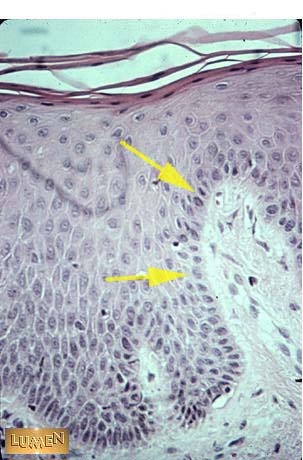

What layer of epithelium does the pointer describe?

Basal